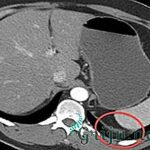

Фото: МРТ заднебоковой грыжи межпозвоночного диска

Для диагностики заднелатеральной грыжи межпозвонкового диска, помимо жалоб пациента и сбора анамнеза заболевания, используется метод пальпации. Выявляется напряжение околопозвоночных мышц, болезненные межостистые связки и паравертебральные точки на уровне поврежденных сегментов.

Характерен положительный симптом "звонка", заключающийся в том, что при надавливании на болевую точку происходит иррадиация боли в зону пораженного корешка. Часто используют рентгенологический метод.

Но для установления окончательного диагноза заднебоковой грыжи диска показано проведение таких методов, как:

- компьютерная томография (КТ);

- магнитно-резонансная томография (МРТ);

- миелография;

- дискография;

- веноспондилография.

Наиболее информативна КТ с миелографией с использованием водорастворимых контрастных веществ.